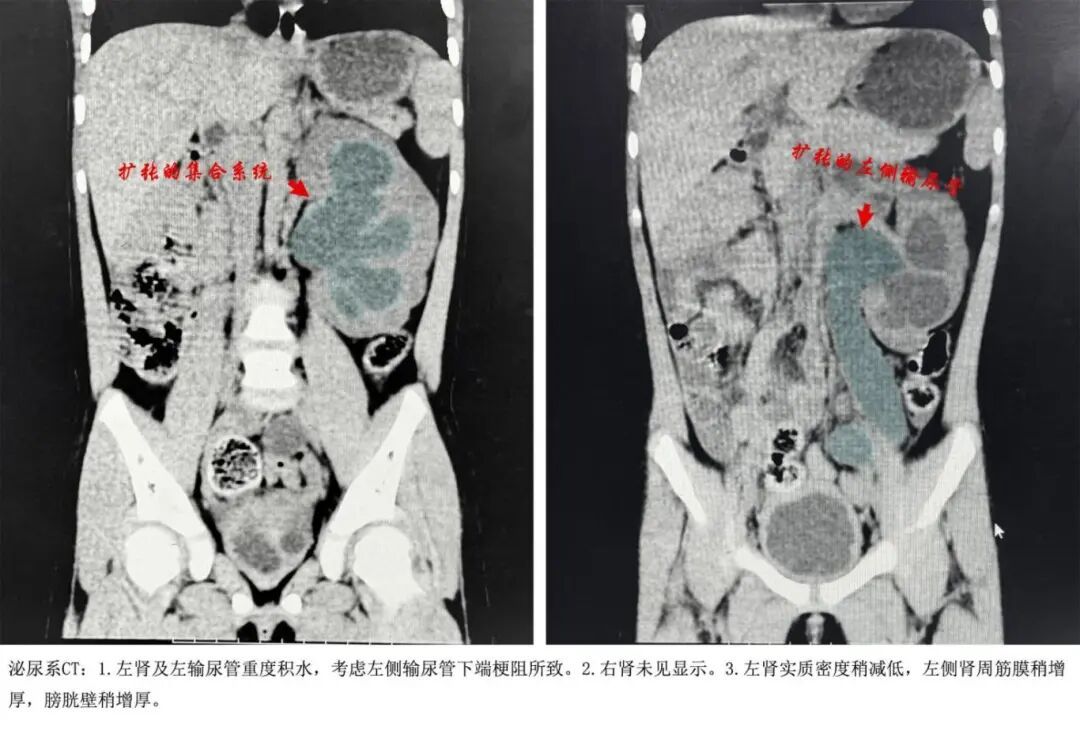

医生检查发现,静静的脸浮肿,左上腹一按就疼,膀胱却是空的。彩超报告让人倒吸一口凉气——体内只发现一个左肾,而且左肾重度肾积水伴输尿管全程扩张,尿液排出的唯一路径(左侧输尿管)堵住了。

魏剑圣安排急查泌尿系CT平扫

提示左肾及左输尿管重度积水

考虑左侧输尿管下端梗阻